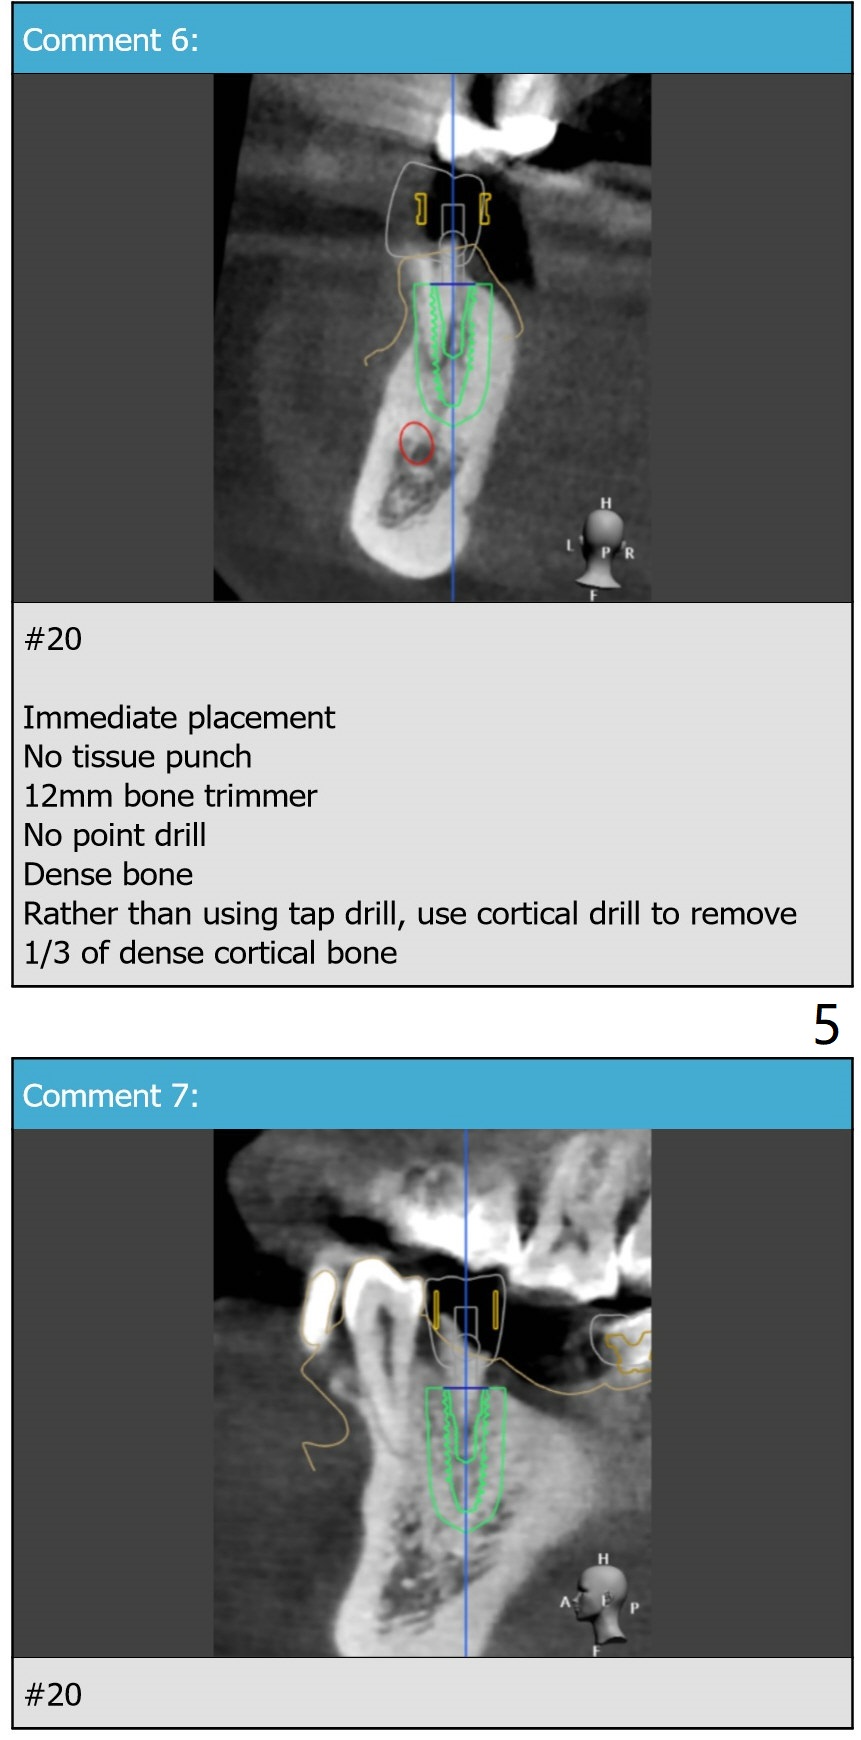

To avoid drill and implant deviation buccally due to the hard lingual plate at #20, use 4.0 mm cortical drill after 3.5x7.3 mm drill. Then resume the normal drill sequence. After implant placement, make sure that they are placed deep enough clinically and radiologically. FC